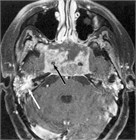

1. 原発巣の進展範囲診断にはCTに加えMRIが推奨される(推奨度2 SJG)